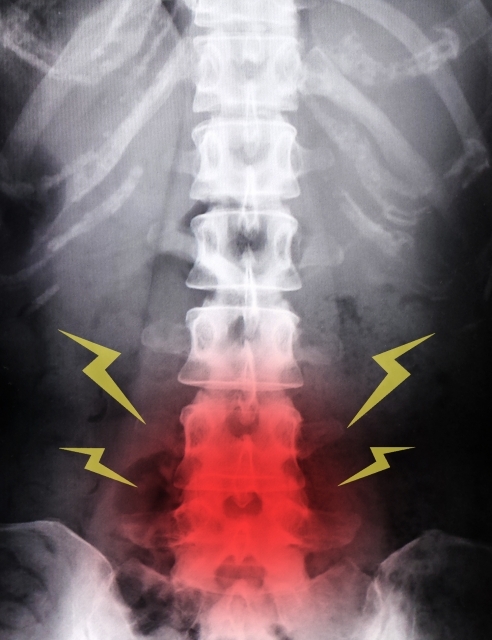

第3章:姿勢や腰痛との関係

骨の密度が低下してくると、体を支える背骨(脊椎)のバランスにも影響が出やすくなります。

「ただの腰痛だと思っていたら、骨の変化が背景にあった」というケースも、整形外科の現場では珍しくありません。体の不調は複数の要因が重なっていることが多いのです。